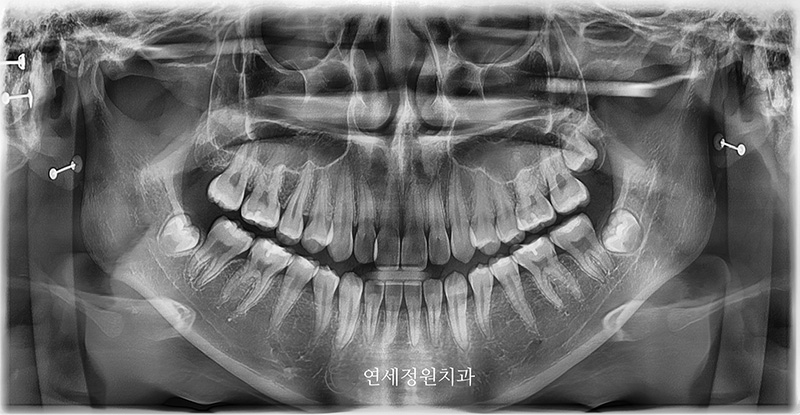

그리고 얼마 전 오랫만에 저희 연세정원치과로 환자분께서 찾아왔을 때는 이미 키가 거의 170cm가 다 된 숙녀가 되어있었습니다 :) (원래 악세서리는 다 제거하고 찍어야 하지만... 엑스레이 상에서도 여기저기 피어싱이 보이네요 ㅎㅎ) 방학이라 한국에 잠시 들른 동안 정기 검진을 받으러 왔는데, 위 앞니 하나가 틀어져 있고 입이 살짝 돌출이라 2차 교정 상담을 하셨으나, 한달 뒤 출국 일정 때문에 부분교정을 하기에도 시간은 부족한 상태였습니다.

2024년 7월